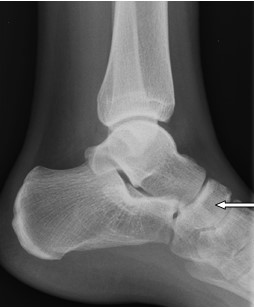

Na rentgenogramie przedstawione jest złamanie Saltera-Harrisa typu

Ilustracja do pytania 19

A. II odcinka bliższego kości piszczelowej.

B. V czwartej kości śródręcza.

C. I ześlizgnięcie bliższej nasady kości udowej lewej.

D. III nasady dalszej kości piszczelowej.